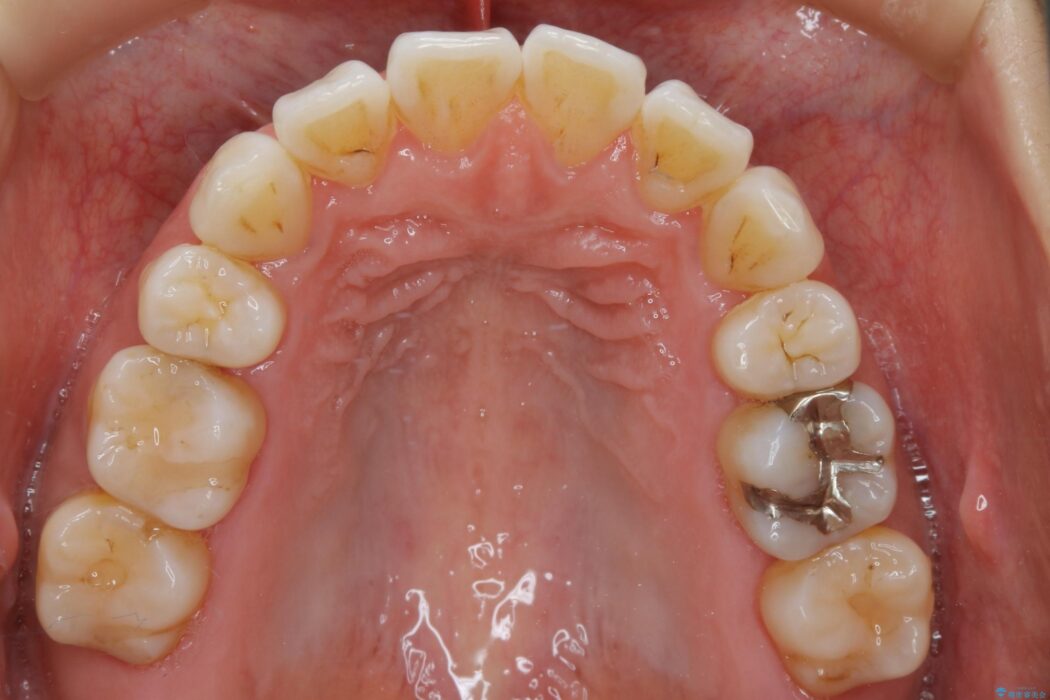

抜歯矯正後の上の前歯の後戻りが気になるとご来院された患者様です。

インビザラインモデレートで治療が可能と診断し、矯正治療を行いました。

歯と歯の間を削るのと、歯列のU字型のアーチを僅かに外側に広げる事でスペースを作り、前歯の角度の改善をしました。